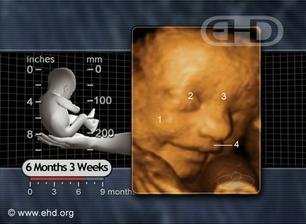

Náš druhý mimísek

Tak Barborce se zatím ven moc nechce.Termín máme zítra ale uvidíme.pAN doktor říká,že to ještě na porod připravené není.Pokud se nic nezmění tak 19.8.jdeme na srdíčko a 22.8.by se šlo na vyvolaný porod.Tak uvidíme jak vše dopadne.Už se ale těším,až to budu mít za sebou hi...